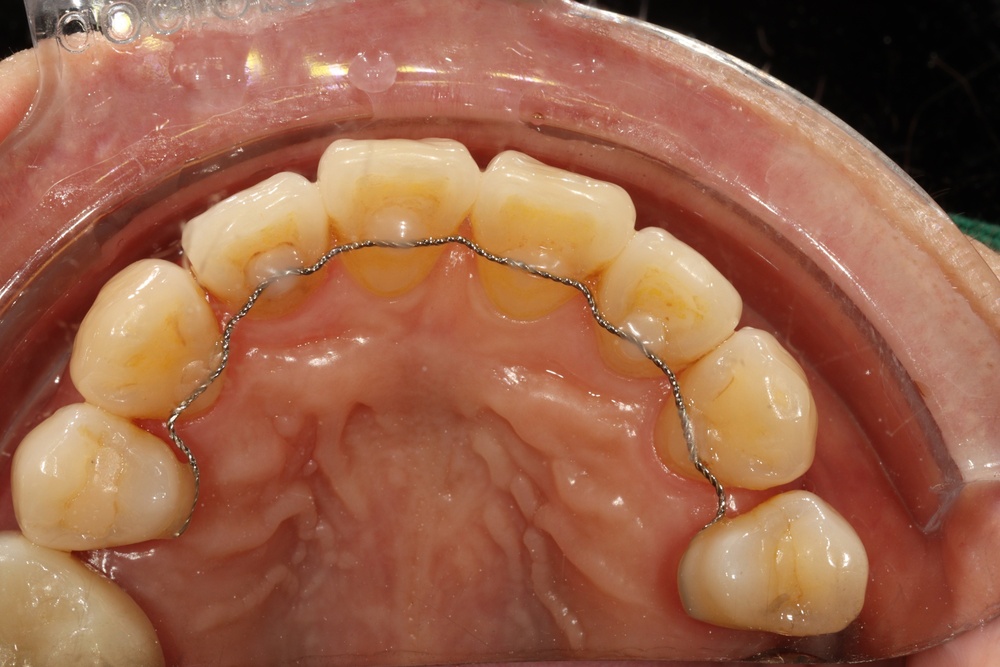

타 치과에서 임플란트 치료중이신 분인데, 교정유지장치 철사(픽스드 리테이너)가 탈락되어서 오셨습니다.

임플란트 진행중인 치과는 교정을 하지 않아서 교정치과로 별도 내원 권유받으셨습니다.

전체 재제작을 위해 기존 유지장치를 제거한 상태입니다.

앞니 잇몸쪽의 벌어짐(블랙 트라이앵글)도 신경쓰인다고 하셔서, 유지장치를 제거하고 레진으로 수복해드리기로 하였습니다.

벌어진 부분을 레진으로 수복하여 틈이 없어졌습니다.

뒤에 교정 유지 철사가 붙어있는 경우 해당치아의 충치치료나 레진빌드업을 위해서는 철사 제거가 필요한 경우가 많습니다.

새로운 교정유지장치 철사도 부착해 드렸습니다.